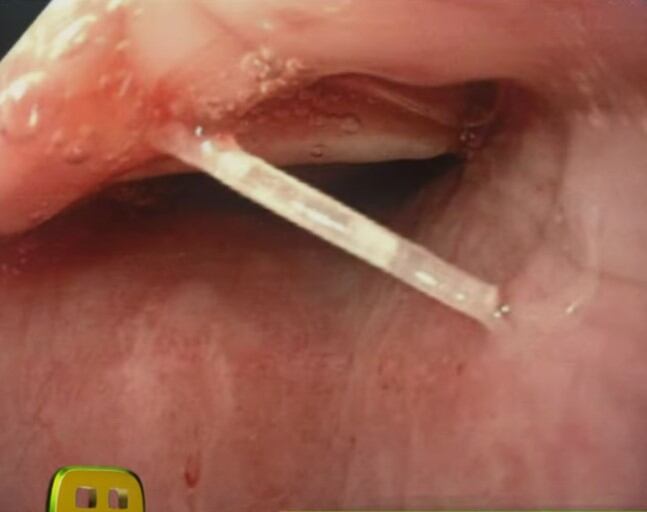

Asimismo, revelaron una perturbadora imagen de lo que encontraron los médicos cuando le hicieron una endoscopía a Linet Puente para que pudiera recuperarse y dejar el hospital.

Así, Linet Puente fue sometida a un lavado de estómago, para quitar todo rastro de alimento y poder retirarle la espina de pescado que obstruía su tráquea, según se aprecia en una foto compartida por ‘Ventaneando’.